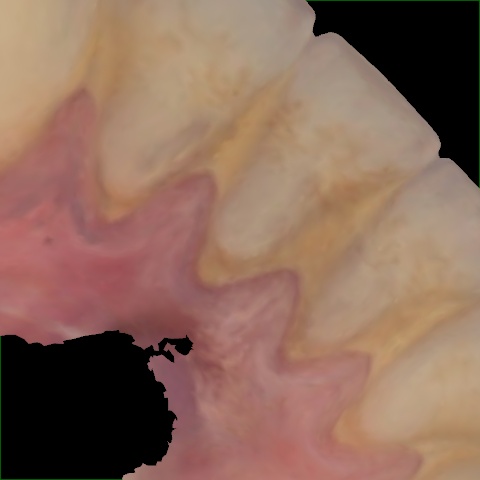

Image 789 / 1527

NHD39455

Annotated as "Good"

Original Image Rendering Image